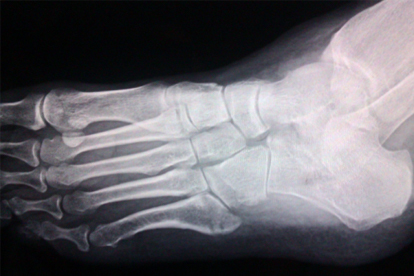

足部撞擊或扭傷可能造成跖骨骨折、韌帶撕裂,表現(xiàn)為局部淤血、壓痛明顯。急性期需冷敷制動(dòng),X線確診后采用石膏固定或手術(shù)復(fù)位?;謴?fù)期可配合跌打丸等中成藥活血化瘀。